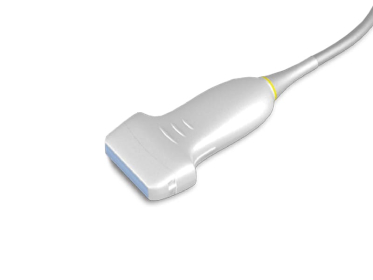

— мультичастотные УЗ-датчики: линейный датчик Edan L742UB, конвексный датчик Edan C352UB, фазированный датчик Edan P5-1b

— линейным L742UB: частотный диапазон датчика 5–10 МГц, апертура 40 мм, глубина сканирования 130 мм, количество элементов 128

- Датчик линейный ультразвуковой L742UB — 1 шт.